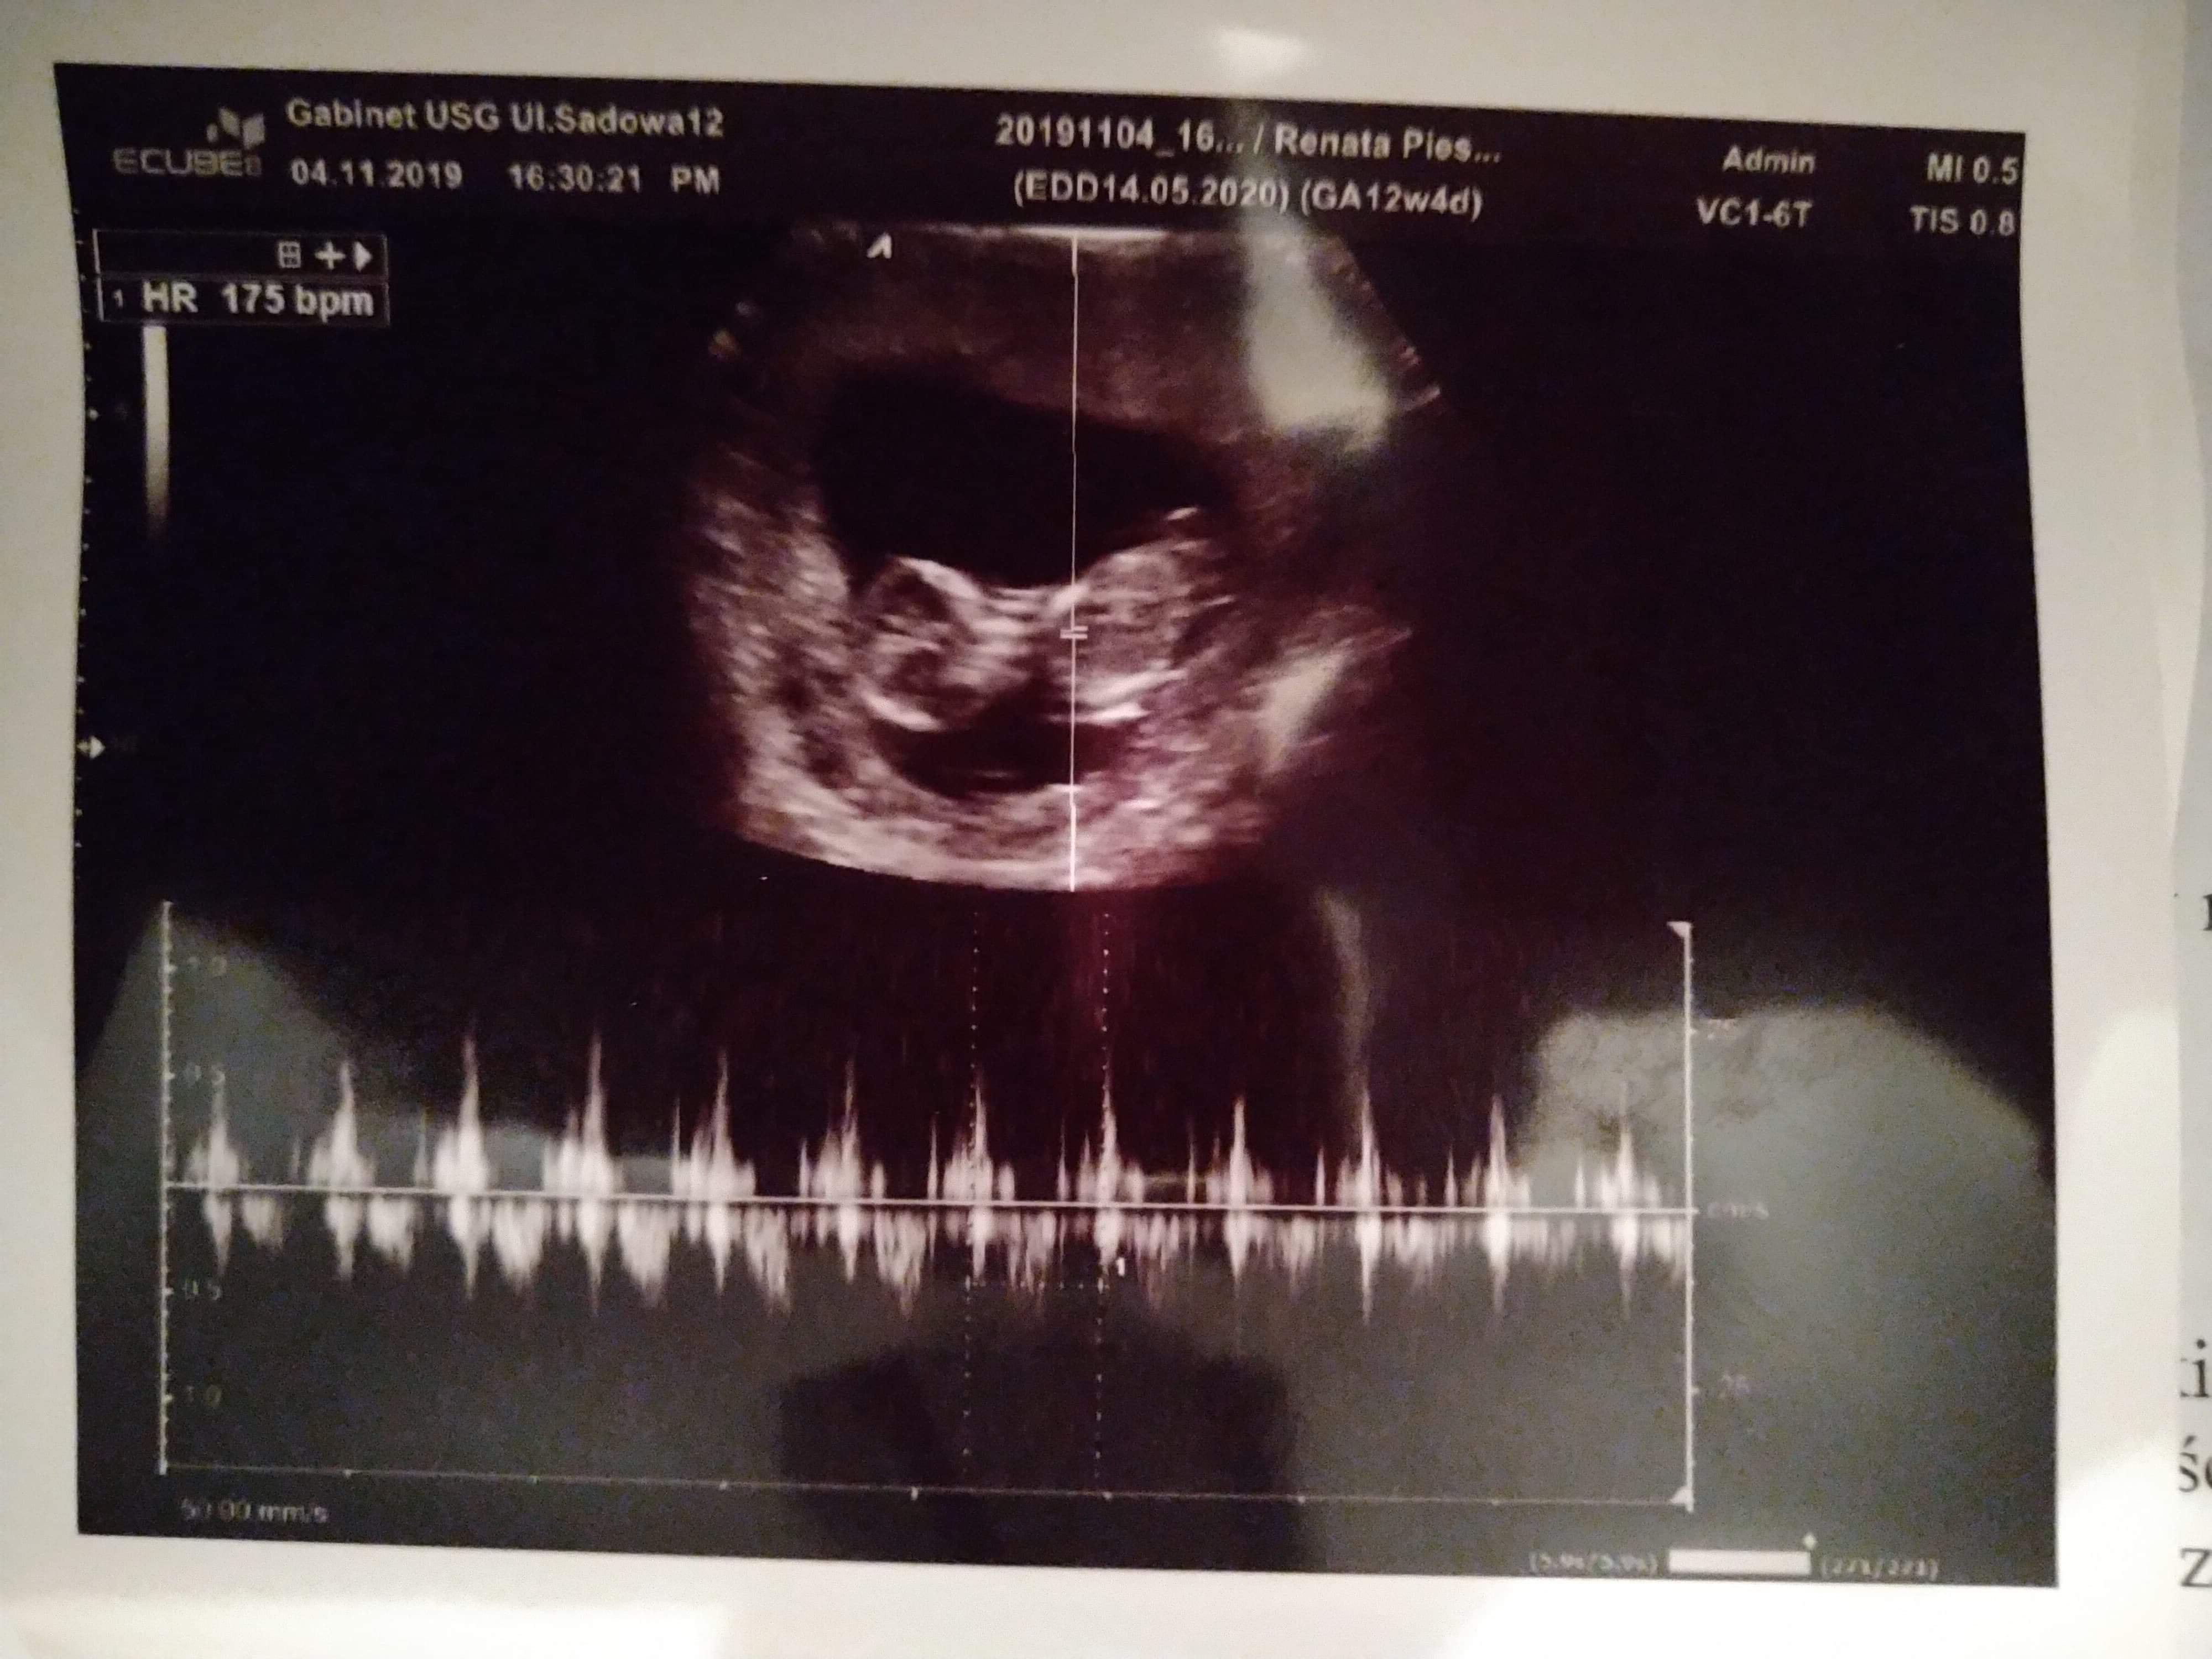

Dziecko ma 6,3 cm. Z USG 12+5, termin 13.05. Z OM 12+4, termin 14.05. Przezierność karkowa 1,04. Tętno 175/min. Nosek jest, rączki nóżki również. Mózg prawidłowo i serducho również. Dziecię jest bardzo ruchliwe i wiercące się. Do tego uparte i charakterne po rodzicach. Nie chciało dać się zmierzyć, ani obrócić z boczku i pokazać. A jak już zaczęło się obracać to tak szybko, że nie dało się nic zmierzyć i ocenić.